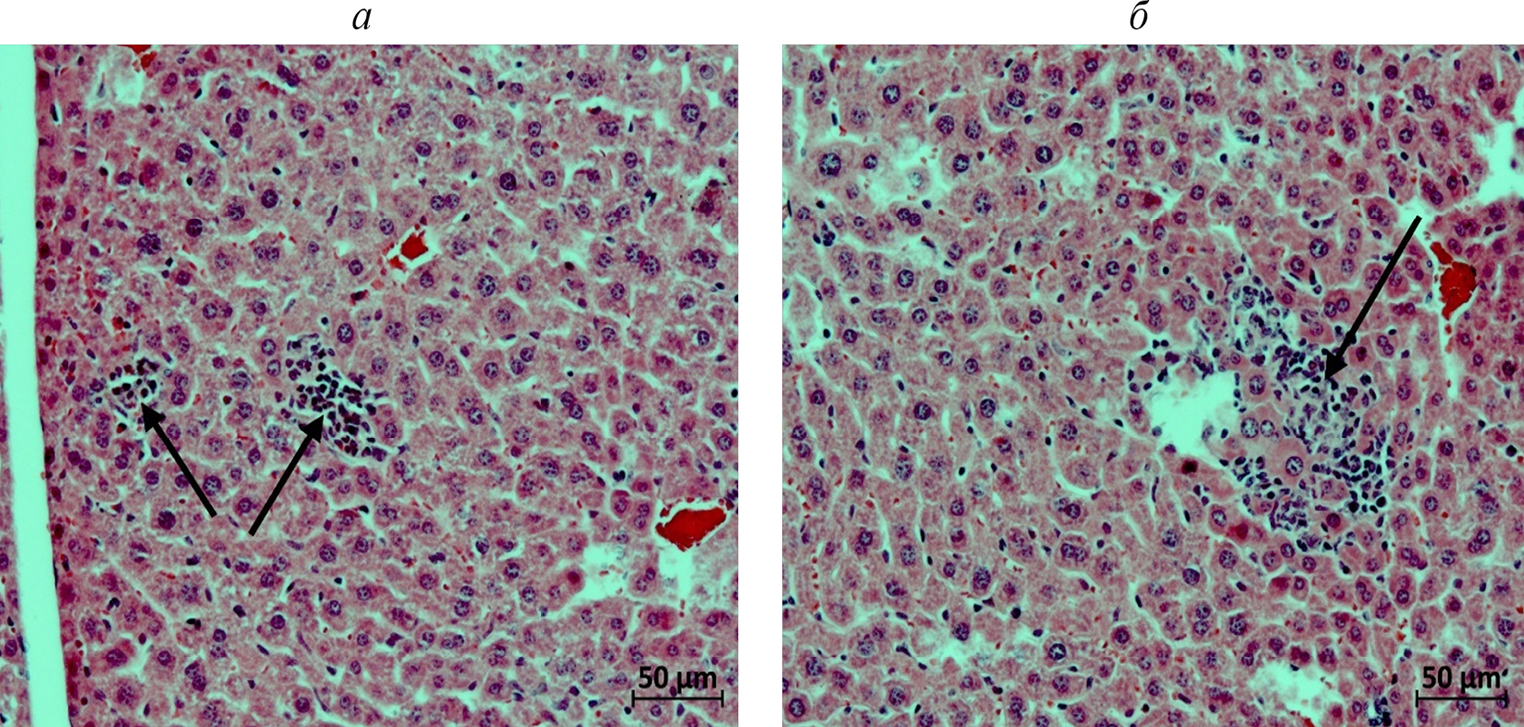

Субхроническая токсичность. Печень. У двух животных контрольной группы (n = 3) в паренхиме разных долей печени обнаружены мелкие очаги мононуклеарной инфильтрации, в одном случае – с явлениями фагоцитоза погибших гепатоцитов и присутствием в части таких очагов сегментоядерных лейкоцитов (рис. 9а). Еще у одного животного не выявлено отклонений функциональной морфологии печени от нормы (рис. 9б). В группе определения субхронической токсичности через 7 дней после отмены препарата выявлены следующие отличия морфофункционального состояния печени от контрольной группы: у четырех животных отмечена очаговая гипертрофия гепатоцитов – у одной самки наблюдались также единичные случаи кариомегалии гепатоцитов и свежие мелкие очаги некроза гепатоцитов в разных долях органа (рис. 10а); у одной мыши обнаружены единичные гепатоциты с пигментными включениями в цитоплазме (рис. 10б); еще в одном случае выявлены многочисленные мелкие очаги экстрамедуллярного гемопоэза в разных долях органа (рис. 10в). У двух животных не отмечено отклонений функциональной морфологии печени от нормы (рис. 10г). Тем не менее, возникновение свежих очагов некроза гепатоцитов у одной мыши спустя 7 дней после окончания введения препарата не позволяет исключить гепатотоксическое действие тестируемого препарата. Однако все остальные изменения функциональной морфологии печени можно отнести к единичным фоновым находкам.

Рис. 9. Фрагменты печени самок мышей контрольной группы. Окраска гематоксилином и эозином. а – Стрелками указан очаг мононуклеарной инфильтрации с сегментоядерными лейкоцитами (мышь 5.4). б – Обычное гистологическое строение органа (мышь 5.3).

Рис. 10. Фрагменты печени самок мышей на 15-й день после 7-кратного введения 1.5 Ед С115Н-PIC-сом МГЛ/2 мг метиина. Окраска гематоксилином и эозином. Стрелками указаны: а – очаг гепатоцитов с начальными явлениями некроза (мышь 4.1); б – гепатоциты с пигментными включениями в цитоплазме (мышь 4.3); в – мелкие очаги экстрамедуллярного гемопоэза (мышь 4.6); г – обычное гистологическое строение органа (мышь 4.7).

Субхроническая токсичность. Почки. Гистологическое исследование почек животных группы субхронической токсичности и мышей контрольной группы не выявило в них каких-либо патоморфологических изменений (рис. 11). Таким образом, ежедневное введение 1.5 Ед С115Н-PIC-сом МГЛ/2 мг метиина (×1) в течение 7 дней не привело к гистологически заметным проявлениям нефротоксического действия препаратов.

Рис. 11. Фрагменты коркового (а) и мозгового (б) вещества почки мыши на 15-й день после 7-кратного введения 1.5 Ед С115Н-PIC-сом МГЛ/2 мг метиина (мышь 4.4). Обычное гистологическое строение органа. Окраска гематоксилином и эозином.

Изменения морфологии печени во всех экспериментальных группах относились к несущественным или слабовыраженным повреждениям/отклонениям от нормы. Отмечено, что исследуемый препарат оказывает негативное дозозависимое влияние на печень: умеренное при однократном введении ×10 терапевтической дозы (ранняя и отсроченная гибель клеток печени) и слабое при однократном введении ×5 и ×1 терапевтических доз (поздняя стадия фагоцитоза погибших гепатоцитов). Низкое гепатотоксическое действие наблюдалось и при ежедневном однократном введении терапевтической дозы в течение 7 дней; морфология печени у четверти животных группы субхронической токсичности не отличалась от нормы. Нефротоксический эффект во всех группах исследования не был обнаружен. Таким образом, фармакологическая пара инкапсулированный фермент С115Н МГЛ/метиин не вызвала существенных отклонений от нормы при исследовании на мышиных моделях и может стать перспективным лекарственным препаратом, способным блокировать развитие патогенных бактерий в организме.